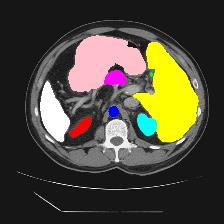

Medical image segmentation is one of the most fundamental tasks concerning medical information analysis. Various solutions have been proposed so far, including many deep learning-based techniques, such as U-Net, FC-DenseNet, etc. However, high-precision medical image segmentation remains a highly challenging task due to the existence of inherent magnification and distortion in medical images as well as the presence of lesions with similar density to normal tissues. In this paper, we propose TFCNs (Transformers for Fully Convolutional denseNets) to tackle the problem by introducing ResLinear-Transformer (RL-Transformer) and Convolutional Linear Attention Block (CLAB) to FC-DenseNet. TFCNs is not only able to utilize more latent information from the CT images for feature extraction, but also can capture and disseminate semantic features and filter non-semantic features more effectively through the CLAB module. Our experimental results show that TFCNs can achieve state-of-the-art performance with dice scores of 83.72\% on the Synapse dataset. In addition, we evaluate the robustness of TFCNs for lesion area effects on the COVID-19 public datasets. The Python code will be made publicly available on https://github.com/HUANGLIZI/TFCNs.